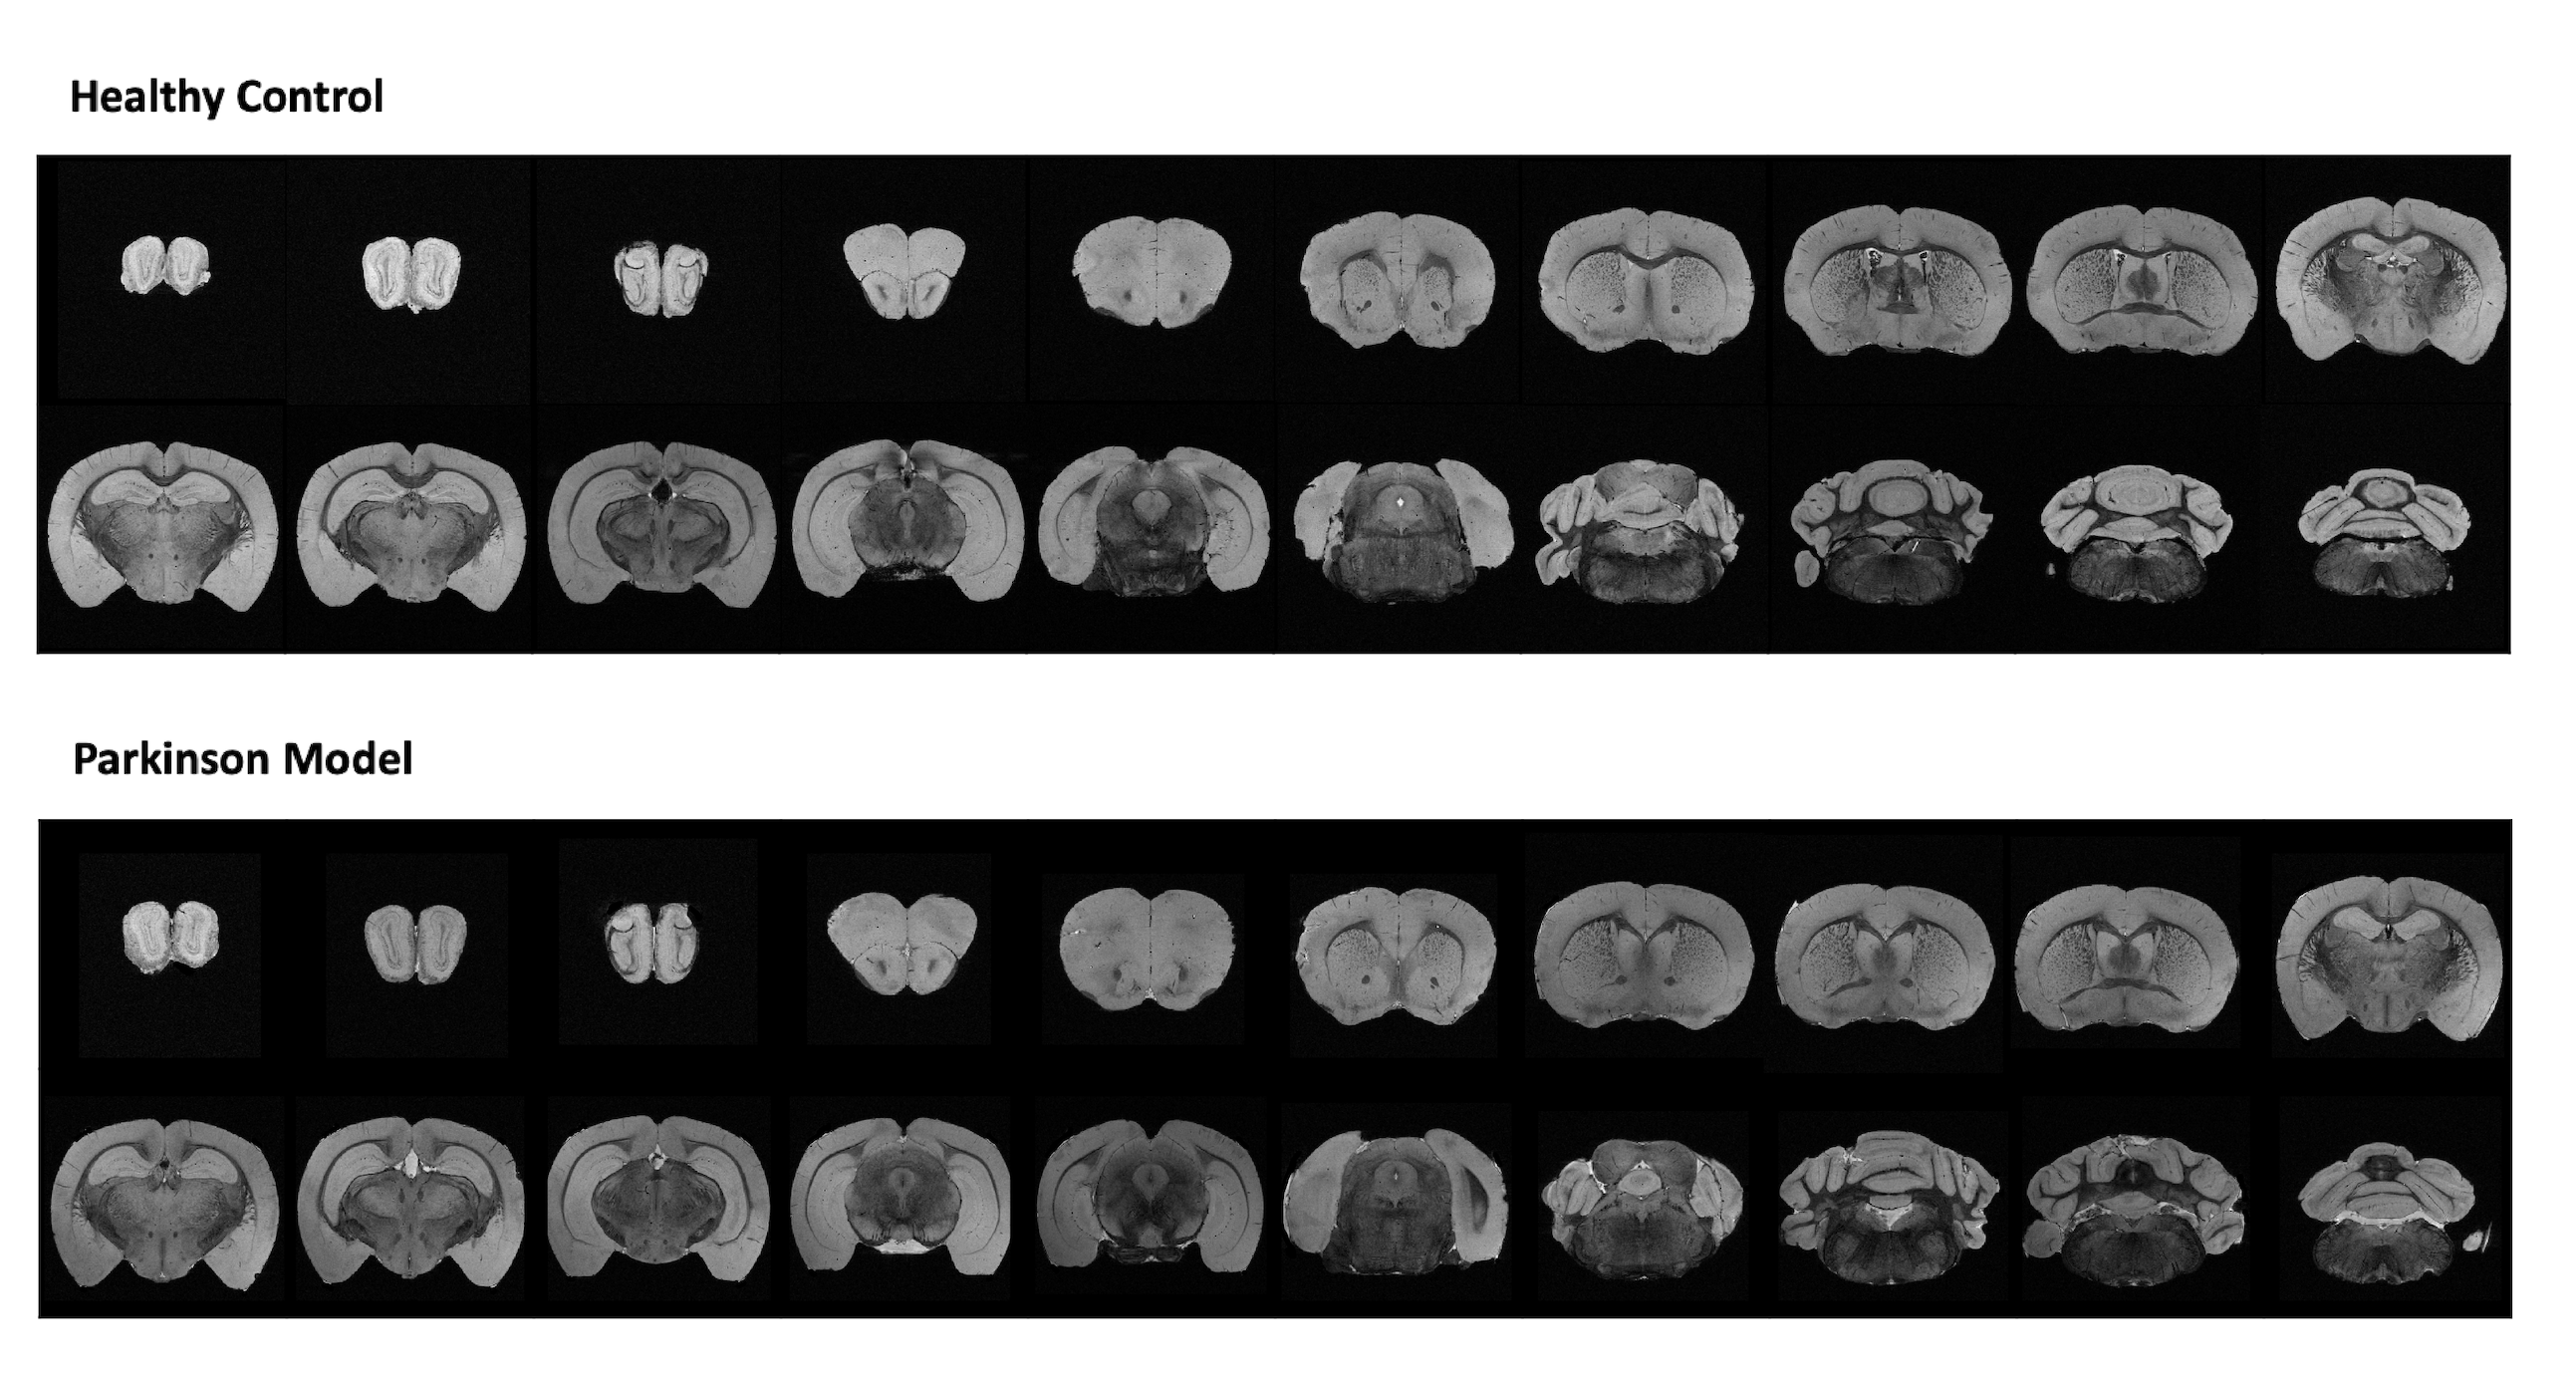

Figure 1 shows MGE’s first echo in 20 slices (out of the 250 slices acquired) covering the entire length of the brain for a representative animal from each group. Signal to noise was above 30 for all specimens.

Figure 1: Anatomical coronal sequential representation of a whole brain structure obtained through MGE MRI sequence at the 16.4T scanner with an isotropic resolution of 40µm. Representative 20 slices out of 250 for each animal were chosen. The upper panel represents a healthy control. The lower panel represents a Parkinson’s Disease mouse model.